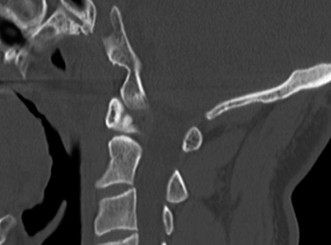

The correct answer is (C). While x-rays and a CT scan may be helpful in evaluating overall alignment of the cervical spine as well as possible bony changes, an MRI would be the best imaging modality to visualize any neurologic involvement leading to the patient’s deficit. With the patient’s history, an infectious etiology is highly likely. While a bone scan can demonstrate increased activity in an area of infection, it does not help localize the exact location and extension of neurological involvement. In the event that an MRI is contraindicated, a CT scan, ideally with

intrathecal contrast, would be a reasonable alternative. Advanced imaging is shown inFigure 1–10. What is the most likely diagnosis? 1. Ossification of the posterior longitudinal ligament

Figure 1–10

The correct answer is (B). The T1 sagittal MRI demonstrates an epidural process that extends behind the C2, C3, and C4 vertebral bodies. There is destruction of the C3–4 disc space, which likely represents discitis/osteomyelitis. The epidural mass is most likely an abscess originating from the C3–4 disc space. OPLL, or ossification of the posterior longitudinal ligament, would typically be seen as an intermediate

signal along the posterior aspect of the disc space/vertebral bodies and would not be associated with disc space destruction. Metastatic tumors and primary bone tumors more commonly involve the vertebral bodies themselves and do not typically cause increased signal within the disc space itself. Extruded disc herniations can extend behind the vertebral bodies but are not as large as depicted in these images and do not lead to signal changes within the disc space with bony involvement.